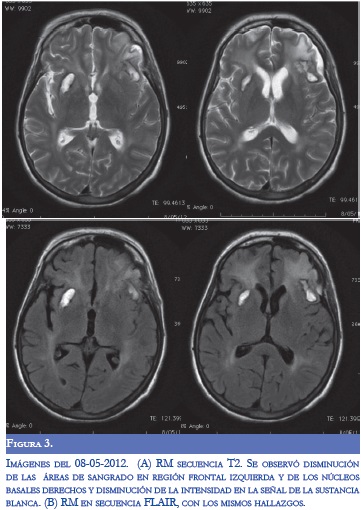

En la evaluación por neurología persistió disnéica con uso de musculatura intercostal, taquipnéica (FR: 32), taquicárdica (120) e inestabilidad hemodinámica (TA: 90/70), alerta con tendencia a la somnolencia, conteo vocal en 13, hipofonía, cuadriparesia 3/5 simétrica e hiporreflexia en 4 extremidades con respuesta plantar felxora bilateral. Se diagnosticó crisis miasténica, con inminencia de falla ventilatoria por lo cual se inició tratamiento con inmunolglobulina G humana y traslado a UCI. Durante la estancia hospitalaria, la paciente presentó respuesta inflamatoria sistémica, con aumento significativo de reactantes de fase aguda y enzimas hepáticas, secundario a bacteremia por Gram negativos, con requerimiento de soporte vasoactivo. Dos días después de finalizar manejo con inmunoglobulina, presentó focalización neurológica con mirada tónica hacia la izquierda, sin respuesta a estimulo externos, ni respuesta nociceptiva. Se realizó TC cerebral donde se evidenció sangrado en región frontal izquierda, otro en región cerebelosa derecha, ambos con edema perilesional, y disminución en la densidad en la sustancia blanca con aspecto de edema vasogénico (Figura 1). En la RM cerebral simple y contrastada se observaron lesiones hiperintensas subcorticales bilaterales con áreas de hemorragia (Figura 2). Se realizó panangiografia cerebral con vasoespasmo de la ACM izquierda M1 y ACA A1 derecha sin patrón de vasculitis. Durante su estancia hospitalaria presentó mejoría clínica y a las dos semanas se observó mejoría del edema vasogénico en las neuroimágenes (Figura 3).